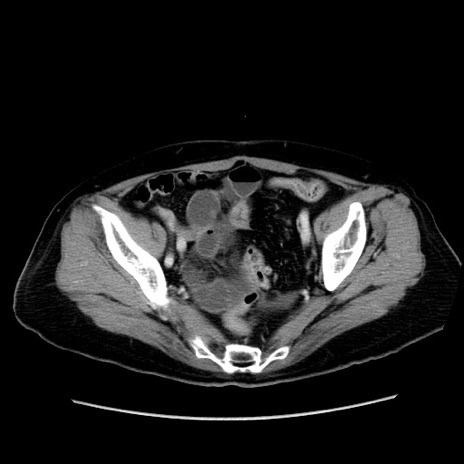

症例19(横断像)

【症例】80歳代女性

【主訴】下腹部痛

【現病歴】約8時間前より下腹部痛の出現あり、救急外来受診。

【既往歴】両側付属器切除

【身体所見】意識清明、下腹部正中に手術痕あり、その部位に一致して圧痛と反跳痛あり。腸蠕動音は亢進。

【データ】WBC 9300、CRP 0.15